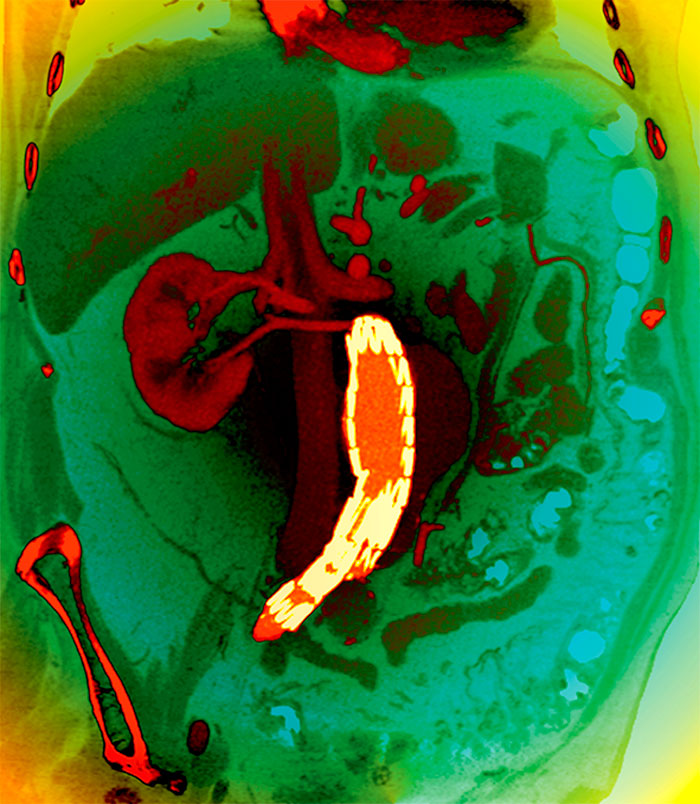

För några år sedan reagerade jag på den information som patienterna i Kalmar län får inför screening för att upptäcka bukaortaaneurysm (AAA). Den är en beskrivning av vad ett aneurysm är, att man inte vet om att man har ett aneurysm, att undersökningen är ofarlig och att aneurysmet kan brista med fara för livet som följd. Det framgår att det »rekommenderas en förebyggande operation«. »Skulle vi hitta en vidgning eller ett bråck på kroppspulsådern vid undersökningen kommer du att få kontakt med en läkare för att diskutera en ytterligare kontroll eller utredning.«

I Cochrane-översikten 2011 [1] »Screening för abdominal aortic aneurysm« sammanfattas kunskapsläget. Den totala dödligheten påverkas inte. Patienter kommer att bli tillfrågade om att ta risken med en operation för ett aneurysm, som med största sannolikhet inte är dödligt. Den psykologiska effekten av screening för såväl patienter som deras anhöriga behöver studeras i detalj.

Redan 1996 konstaterar Ögren et al att prevalensen av AAA är högst bland dem som inte hörsammar kallelsen till screening [3]. Sandefjord et al konstaterar 2011 [4] att förekomsten av AAA har sjunkit sedan 1991 i Nya Zeeland och sedan 1995 i England och Wales med upp till 30 procent. Conway et al konstaterar 2011 [5] att prevalensen av bukaortaaneurysm vid screening var lägre än förväntat, bara 1,7 procent. Svensjö et al [6] finner att vid screening av 22 187 (bortfall 15 procent) svenska män endast 1,7 procent har AAA, mot förväntade 5 procent. En tänkbar förklaring till minskningen av AAA anges vara att män slutat röka, en tanke forskarna delar med flera tidigare författare. De konstaterar att den nuvarande allmänna screeningen kan ifrågasättas. I en ledare i samma nummer av Circulation konkluderar Lederle under rubriken »The rise and fall of abdominal aortic aneurysm« att en screening av män som har rökt med större sannolikhet blir effektiv, till skillnad från allmän screening.